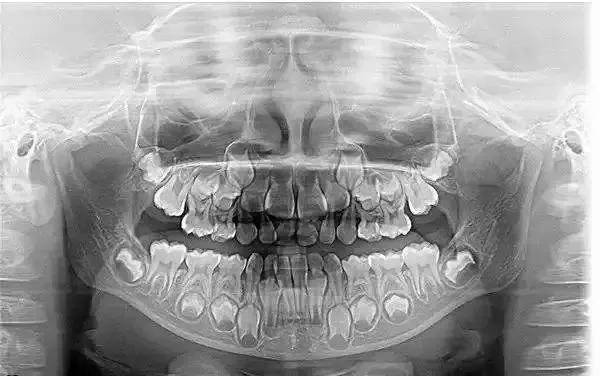

继续说回这次涂氟,当牙医看到宝宝的牙齿时,说宝宝的牙齿护理的相当好!想想就有点小得意,毕竟这3年的小心思没白费。可也有人会说,“宝宝乳牙会换,现在不用那么折腾”。那真是无知者无畏,先看这张图吧!

宝宝还未萌出的恒牙就在乳牙牙根下,可想而知龋齿严重时,恒牙在萌出时很容易龋齿。乳牙虽可换,可恒牙不行。